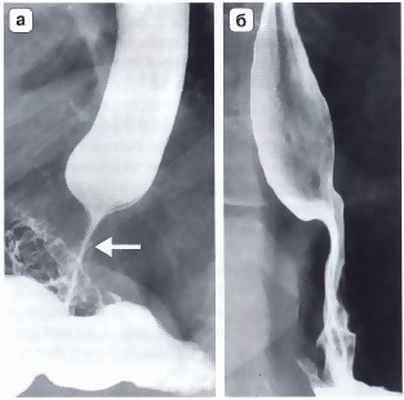

Рис. 3. Рентгенограмма. Осложнения после фундопликация по Ниссену. а — дисфагия, обусловленная излишне туго сформированной манжеткой; б — дисфагия, вызванная излишне длинной фундопликационной манжеткой. В обоих случаях видны признаки нарушения проходимости в области пищеводно-желудочного перехода и супрастенотическое расширение пищевода выше наложенной манжетки (Черноусов А.Ф. и др.)